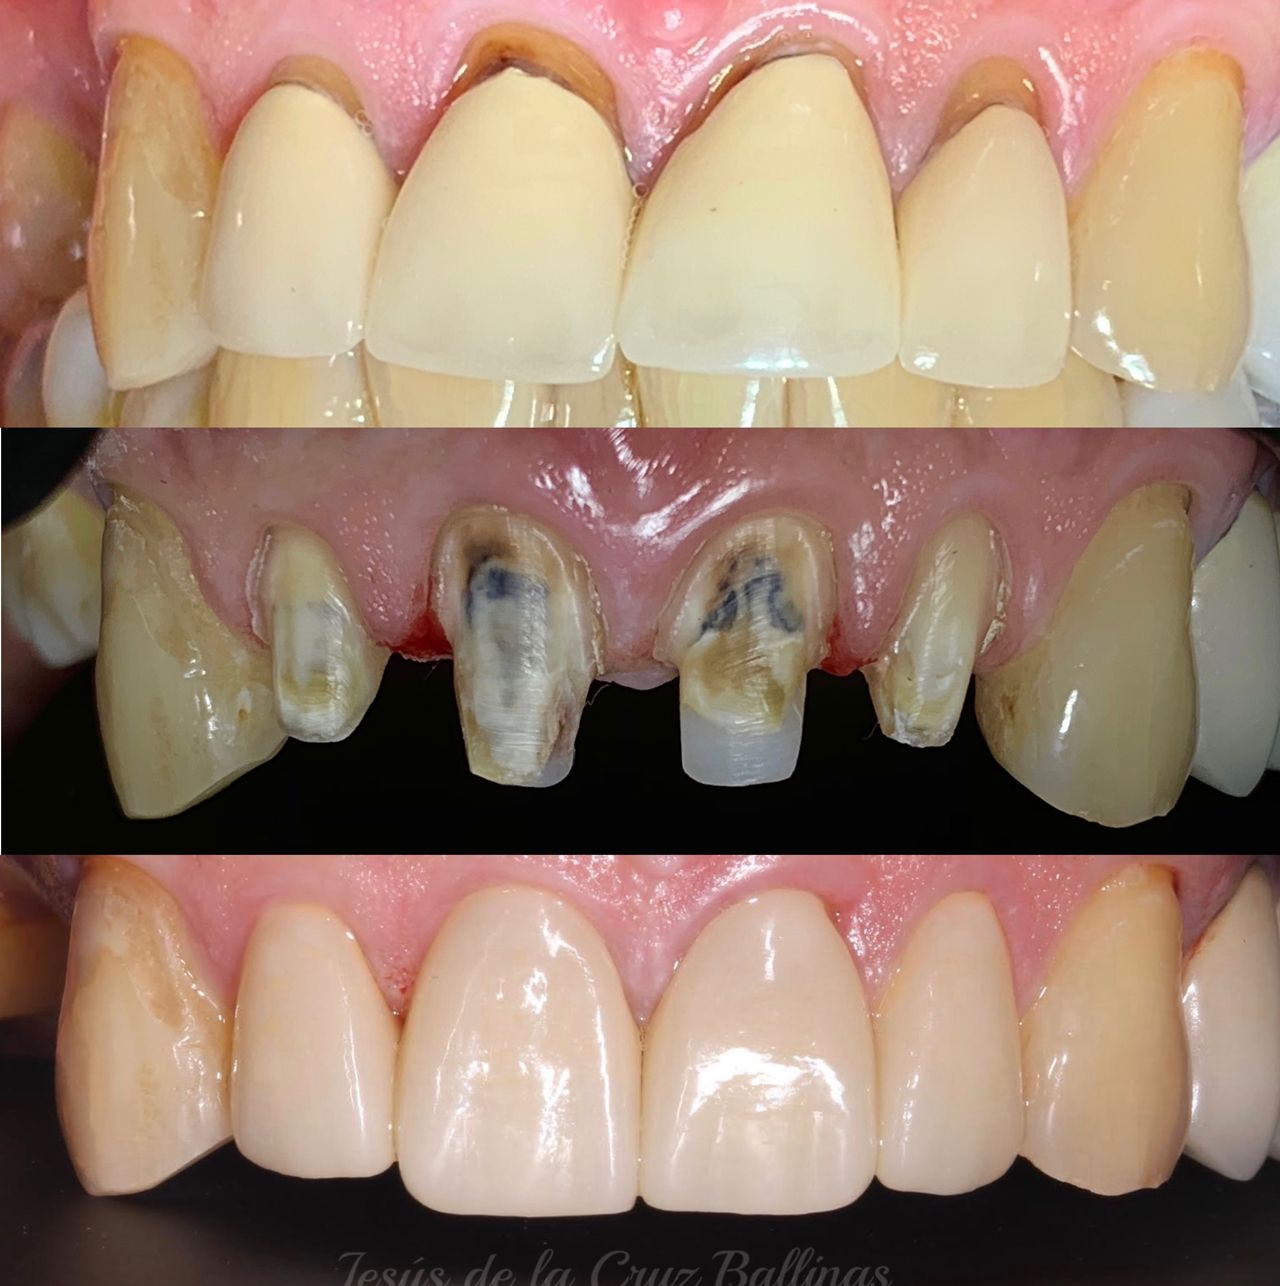

Especialista en Implantología Oral quirúrgica y protesica, cédula de especialidad: 12411844

Especialista en prótesis bucal fija y removible, cédula de especialidad 13216976

La especialidad en Implantología Oral se enfoca en sustituir órganos dentarios perdidos por implantes dentales mediante una fase quirúrgica y una fase protesica y de esta manera devolver la función, estetica y confort dental del paciente.

La especialidad en prótesis Bucal se enfoca en rehabilitar mediante prótesis unitarias, múltiples o totales la función masticatoria de nuestros pacientes brindándoles una mejor estética dental, confort, anatomía dental y función.